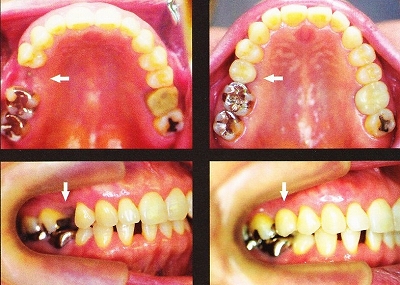

奥歯が無い症例

![]()